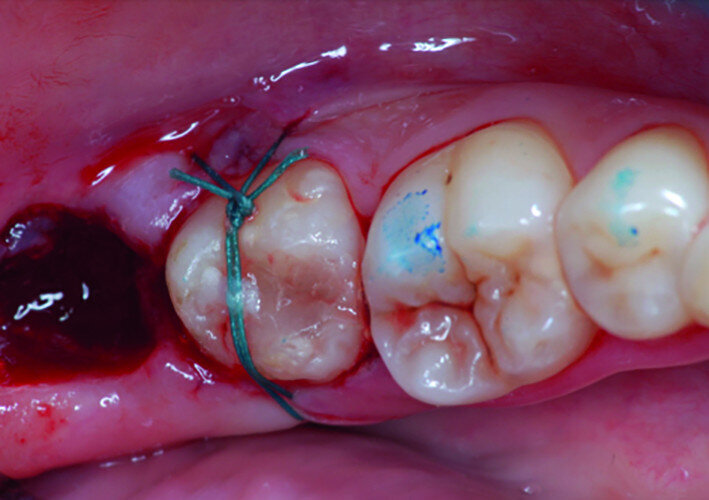

Fig. 8: Transplanted tooth sutured, immediately after surgery.

After local anaesthesia with 2 per cent mepivacaine with 1:100,000 adrenaline, the right maxillary second molar was atraumatically extracted. Initially with a size 15c surgical blade, the periotomy was realised and then the tooth was extracted after separating the roots to avoid unnecessary trauma to the alveolar bone. Then the donor right maxillary third molar was extracted after periotomy as described and transplanted into the adjacent site. Because of the slight differences in the root anatomy, it was necessary to remove the intraradicular bone septum of the receiving site to al- low tooth positioning, and a odontoplastic of the donor tooth crown was performed to maintain it not in occlusion. An antibiotic (amoxicillin/clavulanic acid, 1 g, by mouth twice a day for five days) was prescribed, along with rinses with 0.2 per cent chlorhexidine. The tooth was keep stable with sutures (Fig. 8). A periapical radiograph was taken (Fig. 9). At the suture removal at two weeks, the tooth showed good stability, and positive adaptation of the soft tissue was observed (Fig. 10). At four weeks, the tooth was stable and the soft tissue looked healthy (Fig. 11). The patient did not show any adverse effects and stated that the tooth was fully functional. Examination of the avulsed second molar showed the extent of the perforation (Figs. 12 & 13).